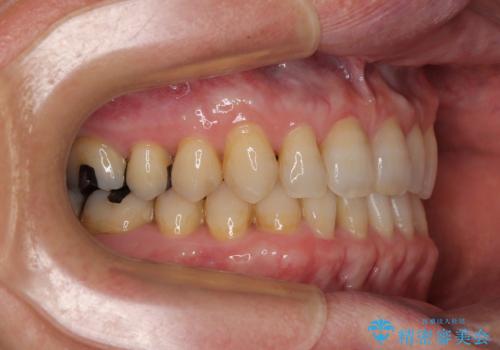

- 前歯のデコボコと隙間の空いた歯列を気にして来院された患者様です。

下顎前歯が隠れるほどのディープバイトにより、強い咬合力と突き上げで上顎歯列に隙間が空いている状態でした。

ディープバイトが改善され、睡眠時の食いしばりも緩和され、顎への負担が軽減されました。